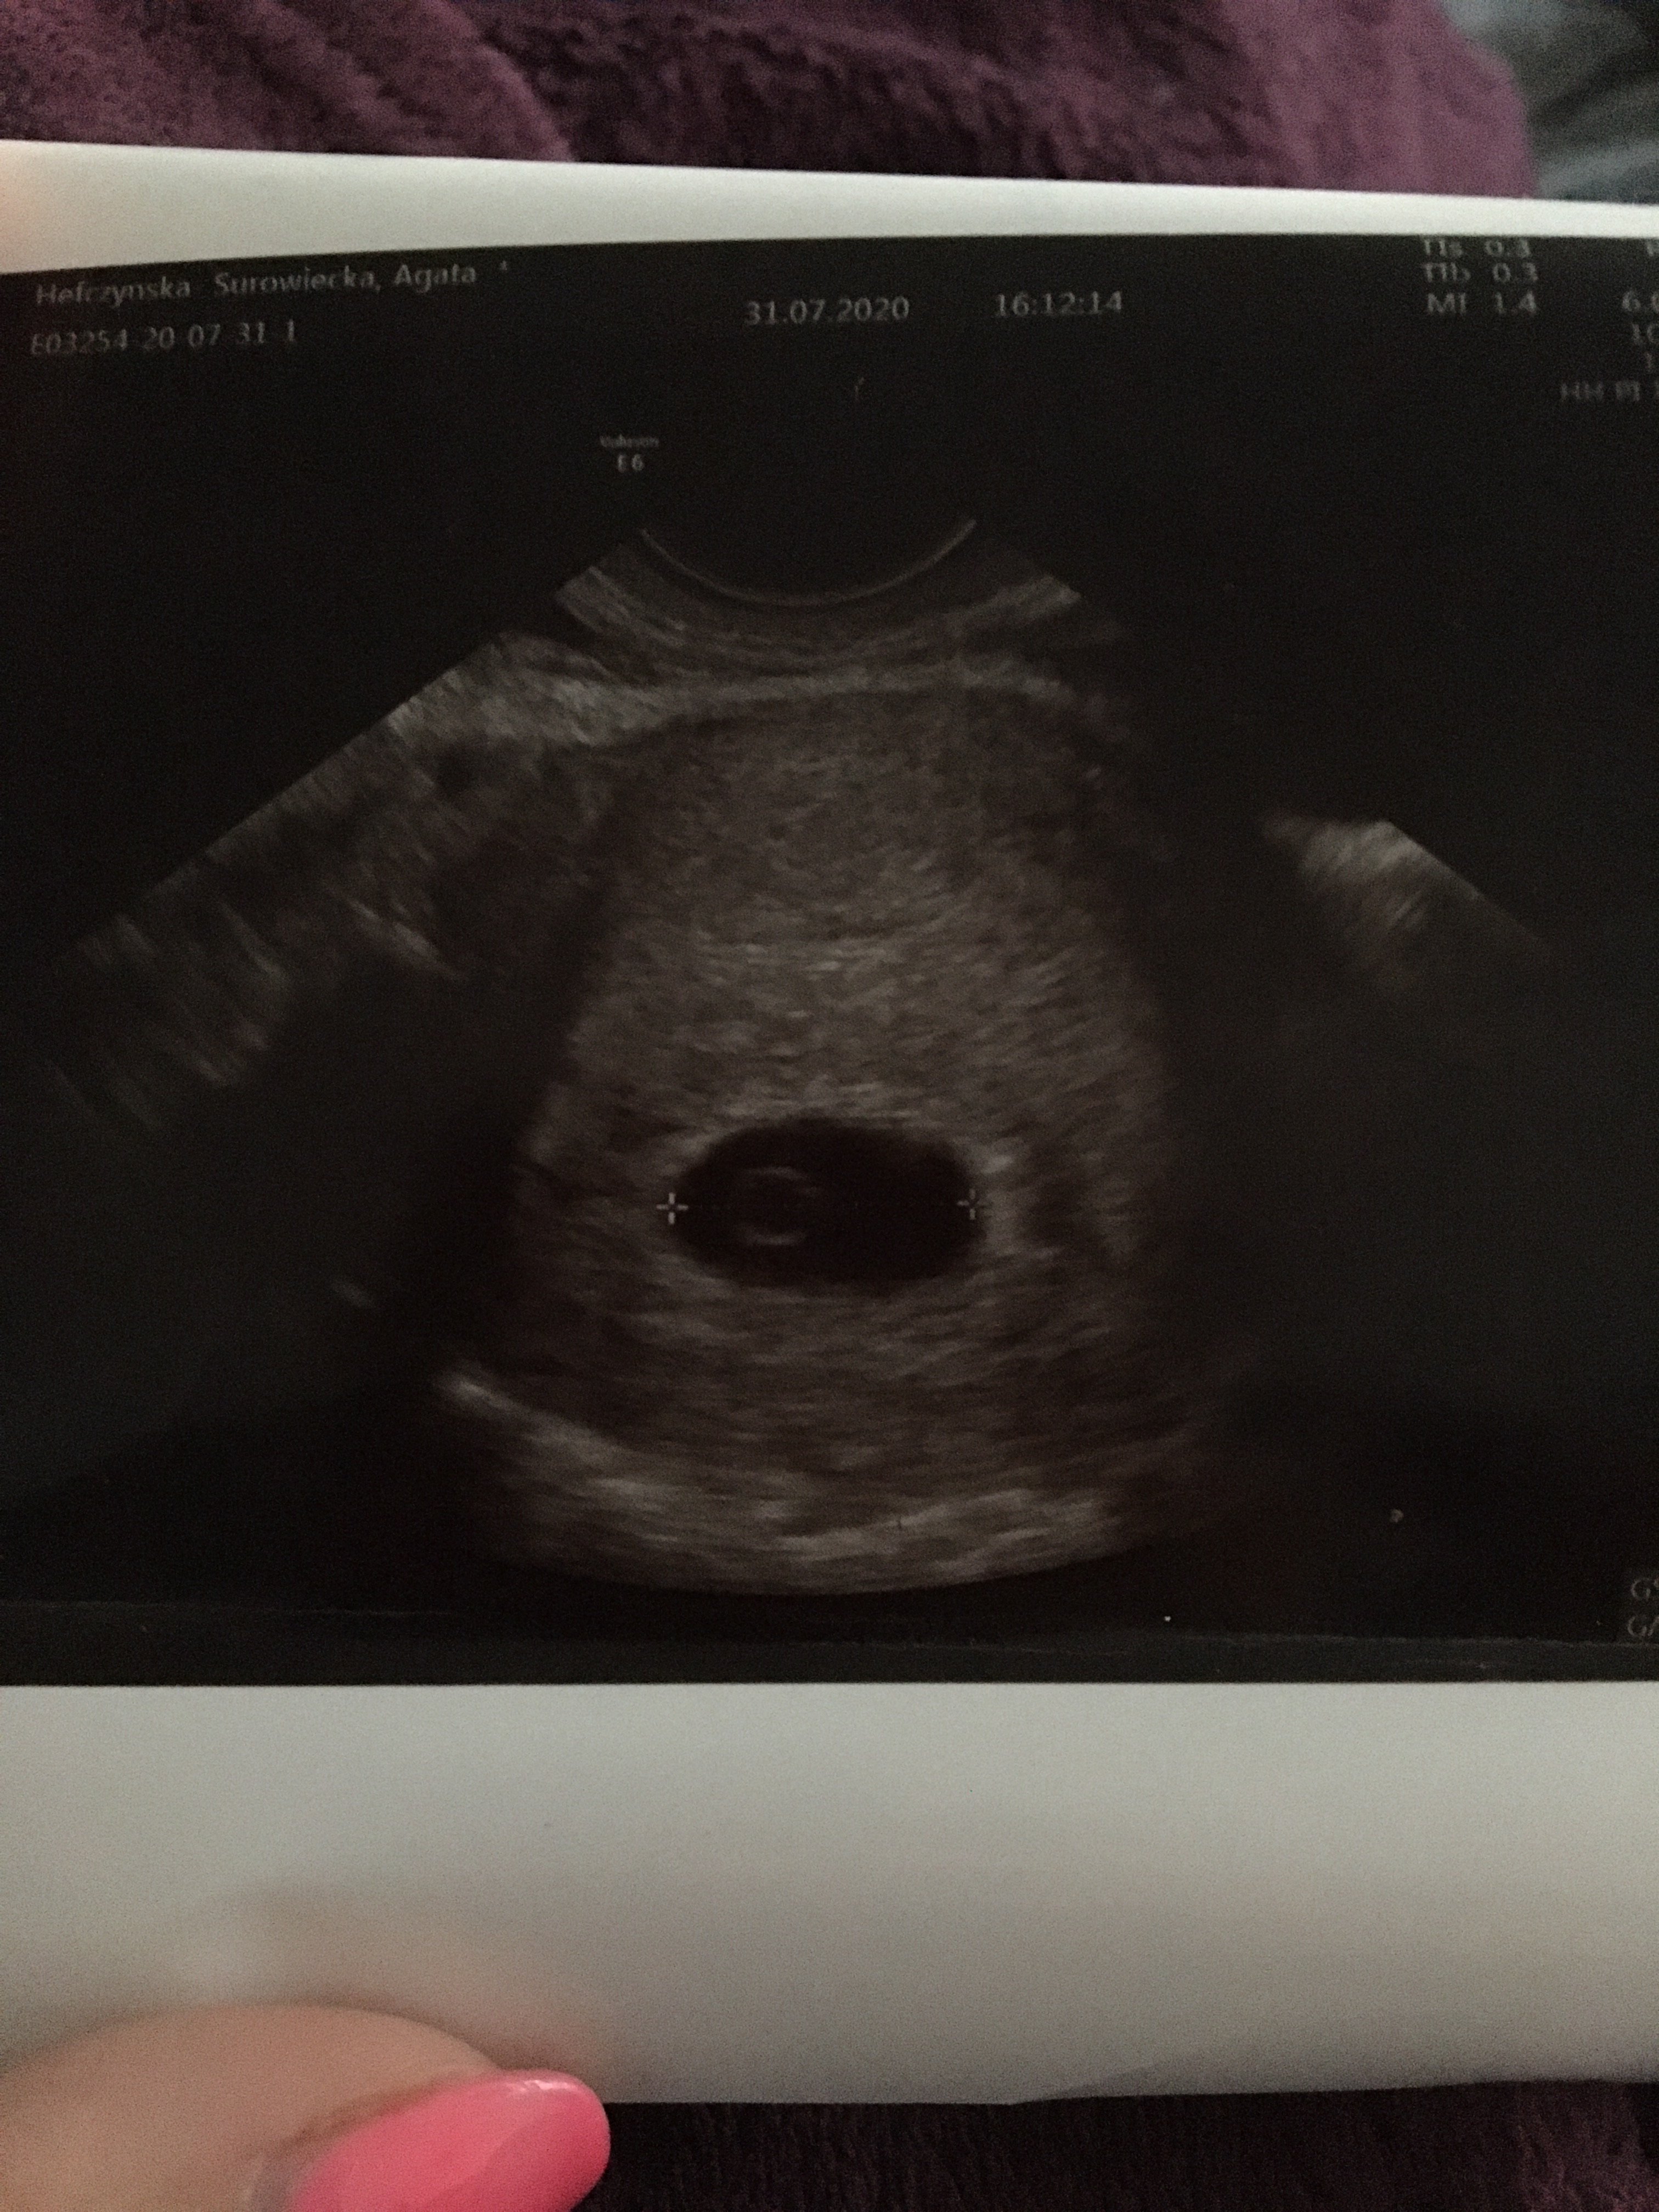

Serduszka chyba nie było tzn lekarz był bardzo oschły i nie dawał dojść do słowa, tak wyglada usg 6,1 dzień. Czy uważacie ze to nie jest dziwne ze jest tylko taki pęcherzyk ?

• image.jpg

image.jpg

1,8 MB · Wyświetleń: 6 708